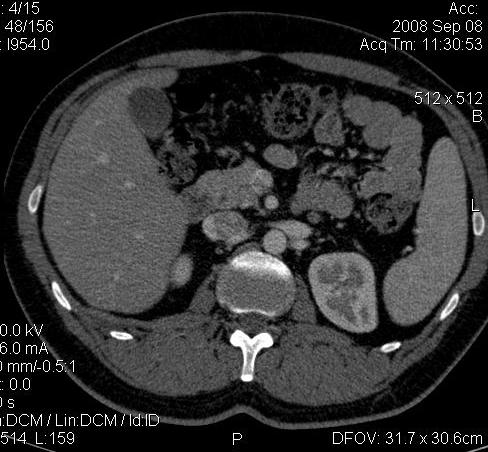

КТ Почек- подкова и уретеролитиаз

Данное наблюдение весьма демонстративно само по себе.

Ну ладно, раз никто больше не хочет, то отвечу свою версию - аномалия развития - подковообразная почка (horseshoe kidney).

Да красивая подковообразная почка - встречала раз 6-7.

Не вызывает сомнений. Картинка замечательная. Должно быть хорошо видно и на УЗИ.

Почечная колика; на последнем аксиальном скане чётко виден мелкий (2 мм) камень в устье правого мочеточника.